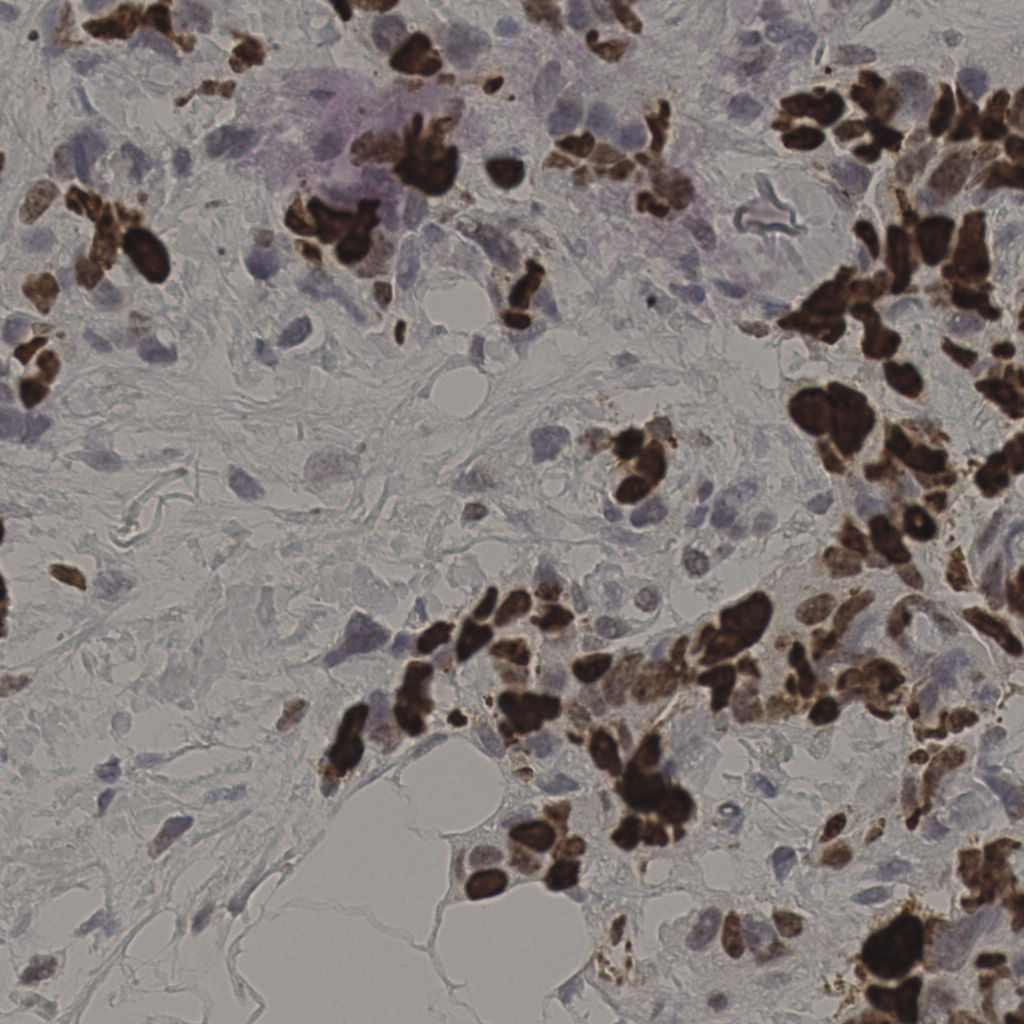

17.75%

Ki67 指数

阴 7986 阳 1723

切片统计

总切片 2640

有效 412

已标记 412

有效率 16%